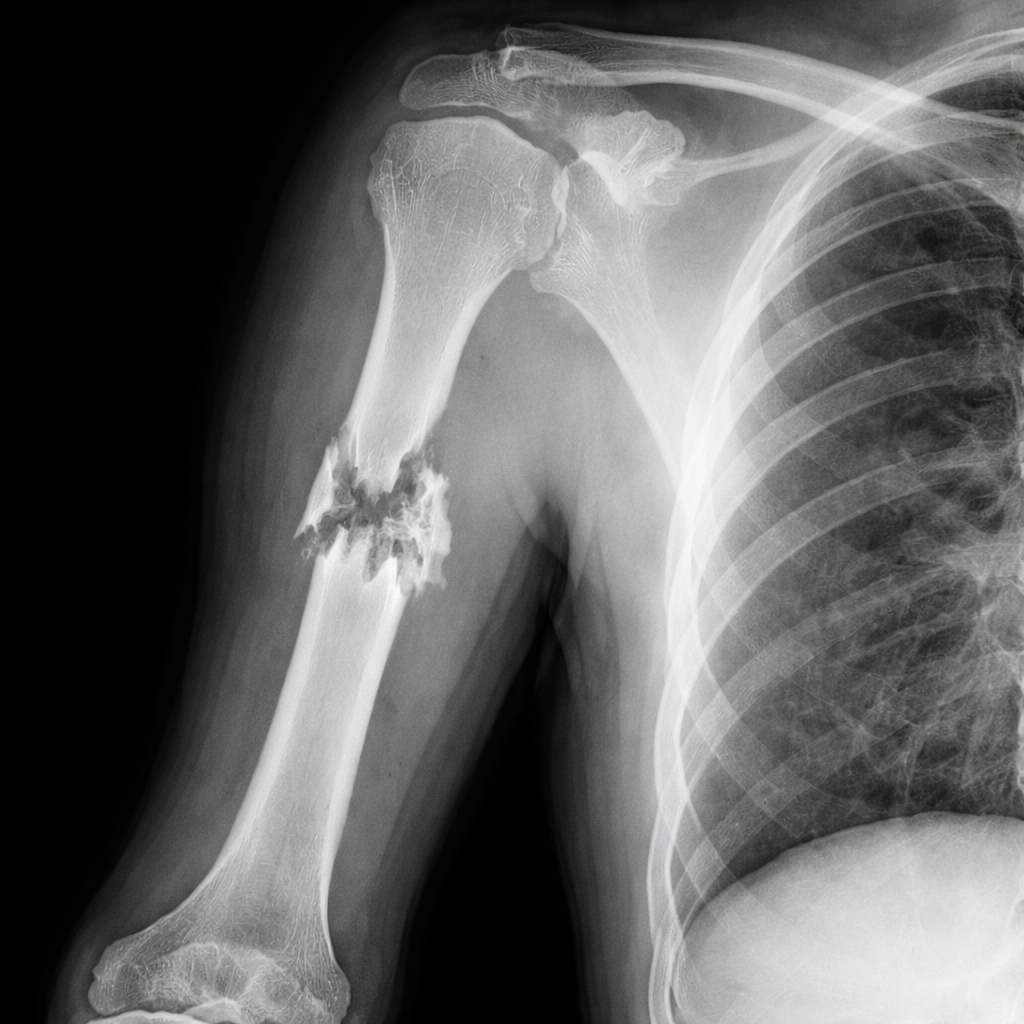

RTG (rendgenska dijagnostika) je osnovna i široko primjenjivana dijagnostička metoda koja omogućava brz i pouzdan uvid u stanje kostiju, pluća i drugih struktura tijela. Zahvaljujući brzini i dostupnosti, RTG je često prvi korak u postavljanju dijagnoze.